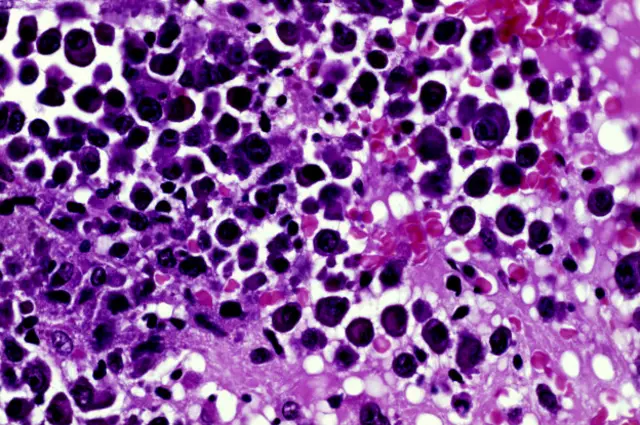

И "Ревлимид", и "Метибластан" - торговые наименования иммуномодулирующего препарата леналидомид, который используется для лечения множественной миеломы. Это заболевание системы крови, при котором в костном мозге собираются аномальные плазматические клетки: они препятствуют производству нормальных клеток крови и приводят к поражению костей.